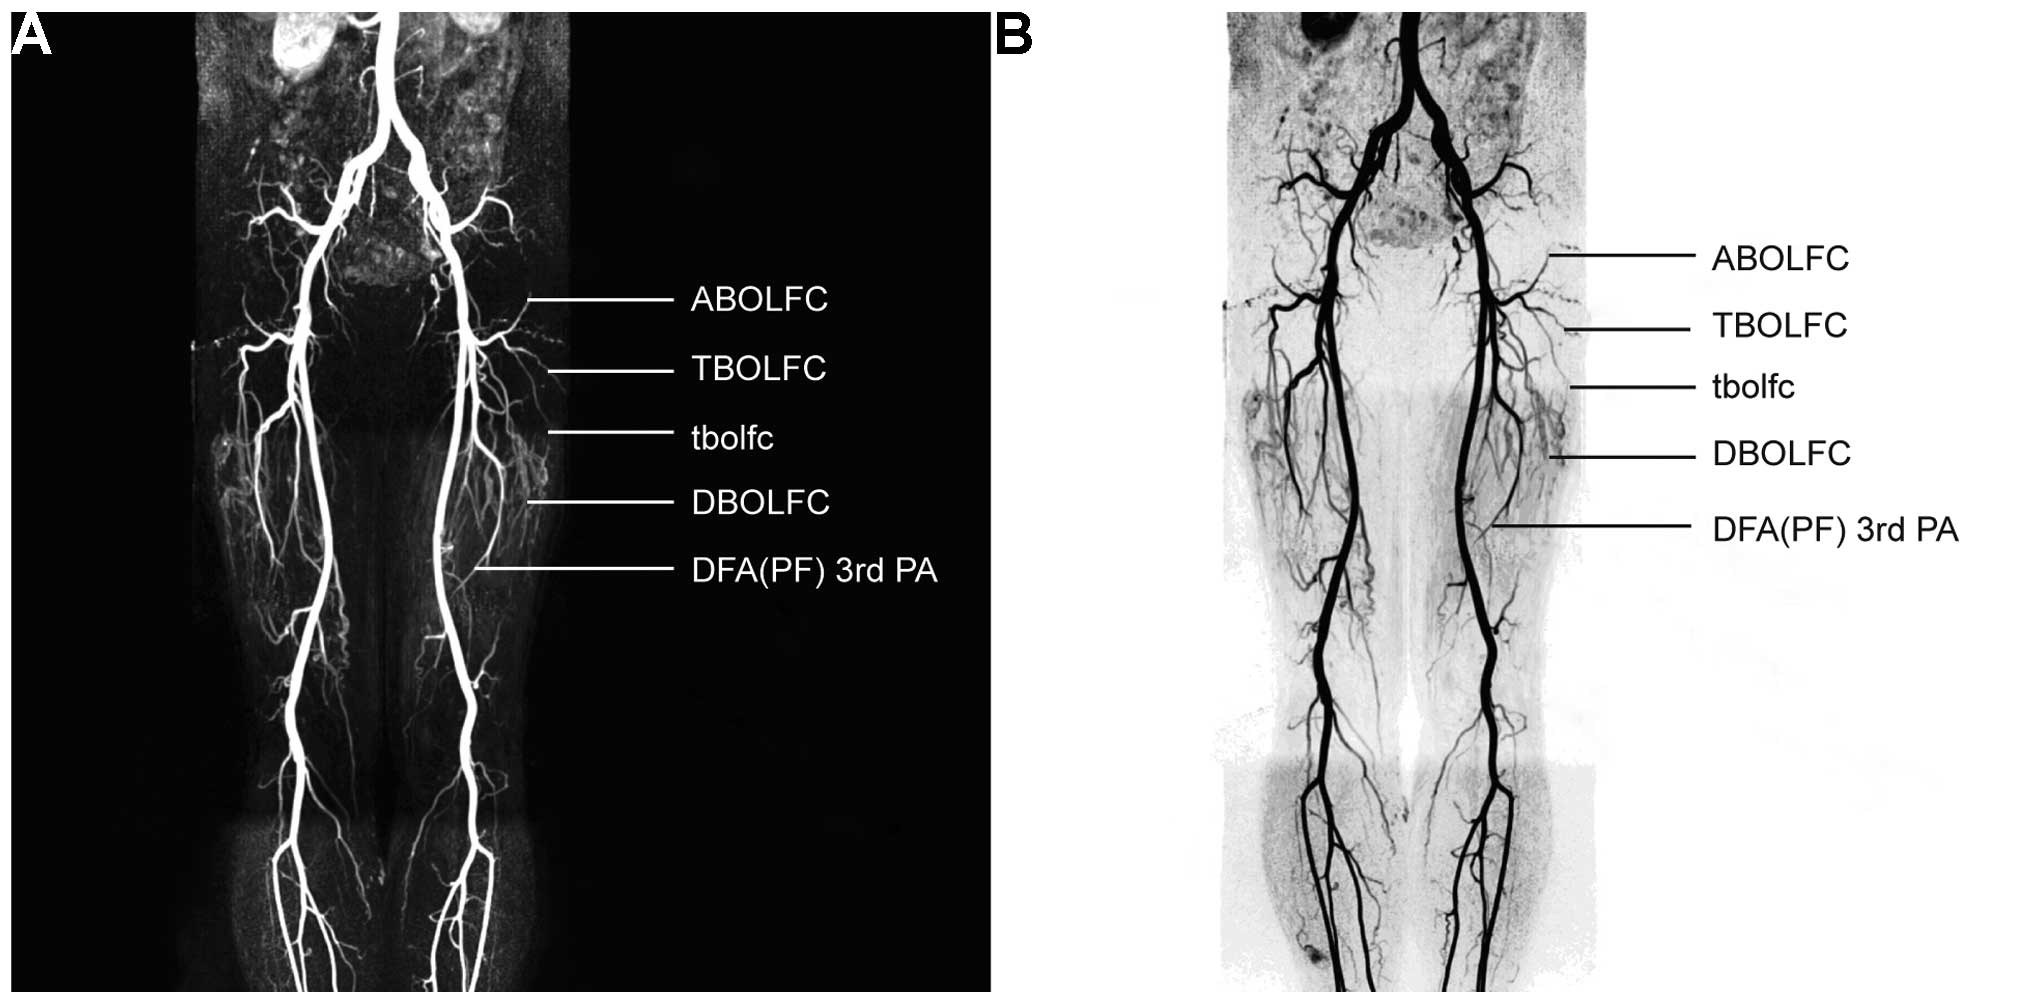

As shown in Table I, the LFCAs of the bilateral lower limbs were well visualized by 3D-CE-MRA in all 68 patients. The anatomical pattern of the LFCA was type Ia in 80 cases (58.8%), type Ib in 21 cases (15.4%), type II in 20 cases (14.7%), type III in 3 cases (2.2%) and type IV in 12 cases (8.8%). Tertiary vascular trees (primary, main trunk of LFCA; secondary, ascending, transverse and descending branches; tertiary, muscular perforating vessels) were identified in 94 limbs (69.1%). The intermuscular orientation of the perforating vessels was also clearly shown with MRA. The length of the descending branch vascular pedicle (the linear distance from the origin of the branch to the distal end) ranged from 41 to 323 mm. As shown in Fig. 1A and B, the left LFCA (type Ia) originated from the left DFA and subsequently trifurcated into the ascending, transverse and descending branches. As shown in Fig. 2A and B, the right LFCA (type Ib) originated variably from the right DFA and subsequently trifurcated into the ascending, transverse and descending branches. As shown in Fig. 3A and B, the descending branches of the bilateral femoral circumflex arteries converged with the ascending branch of the bilateral superior genicular arteries. Type Ib LFCA, i.e. an LFCA originating variably from the FA, was identified in 21 cases. Among these cases, TS-MIP reconstruction of the opening portion of femoral artery revealed the specific origin of the LFCA to be from the anterolateral part of the FA in 10 cases and from the posterolateral part of the FA in 11 cases, and another from the inferior part of the DFA in 19 cases.

Figure 1.

Type Ia LFCA. (A) Three dimensional-contrast-enhanced magnetic resonance angiography reconstructed maximum intensity projection and (B) digital subtraction angiography images showed that the LFCA originated from the DFA and subsequently trifurcated into the ascending, transverse and descending branches. LFCA, lateral femoral circumflex artery; DFA (PF), deep femoral artery (profunda femoris); ABOLFC, ascending branch of the LFCA; TBOLFC, transverse branch of the LFCA; DBOLFC, descending branch of the LFCA.